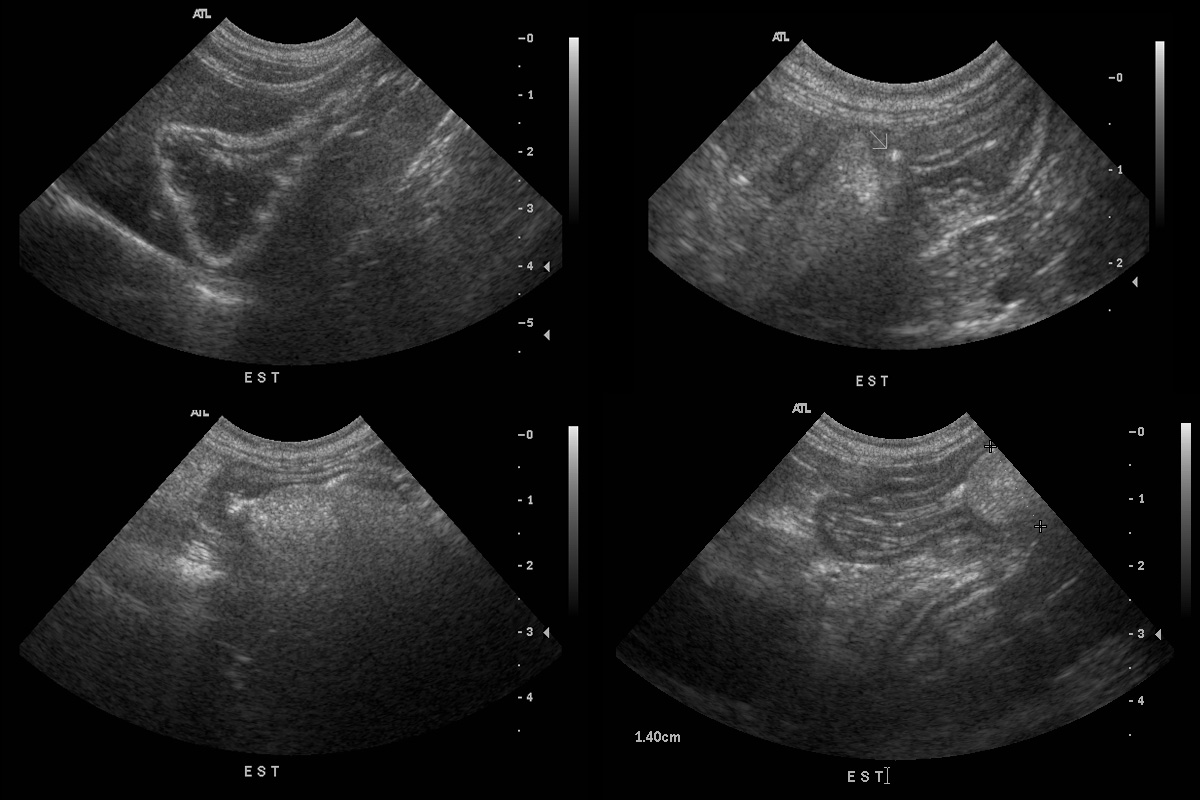

CE estomac chat